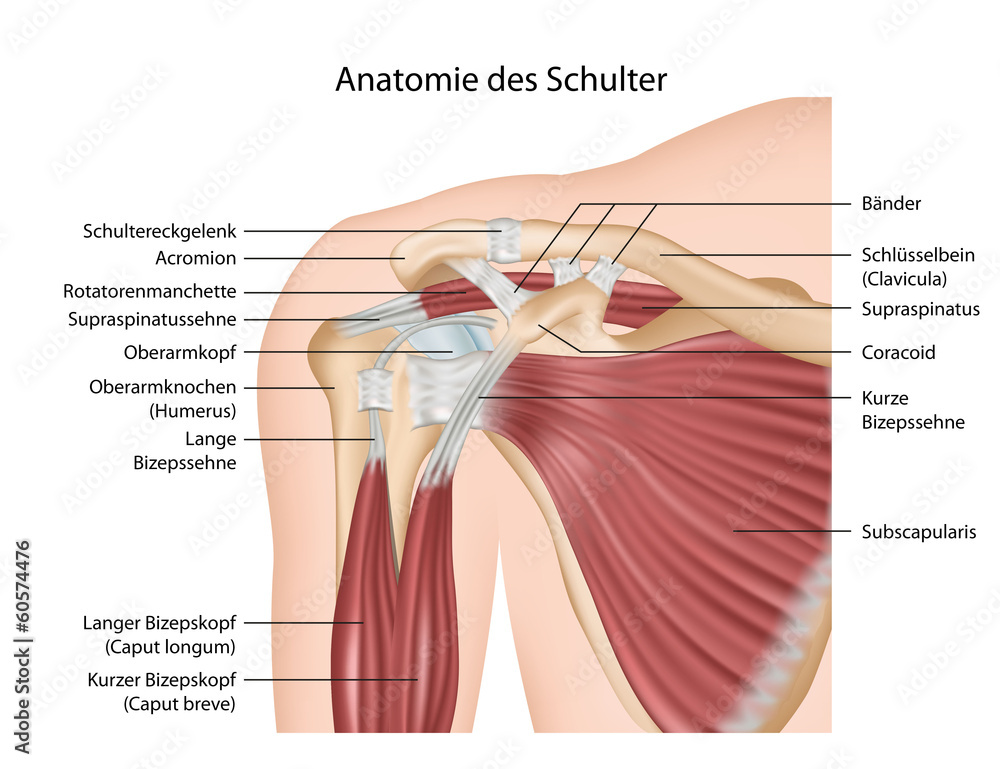

Фотографии поддельтовидной мышцы плечевого сустава